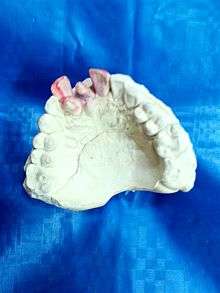

| Supernumerary teeth in the premaxillary area | |

Hyperdontia is the condition of having supernumerary teeth, or teeth that appear in addition to the regular number of teeth. They can appear in any area of the dental arch and can affect any dental organ.

Supernumerary teeth can be classified by shape and by position. The shapes include the following:

When classified by position, a supernumerary tooth may be referred to as a mesiodens, a paramolar, or a distomolar.[1]

The most common supernumerary tooth is a mesiodens, which is a malformed, peg-like tooth that occurs between the maxillary central incisors.